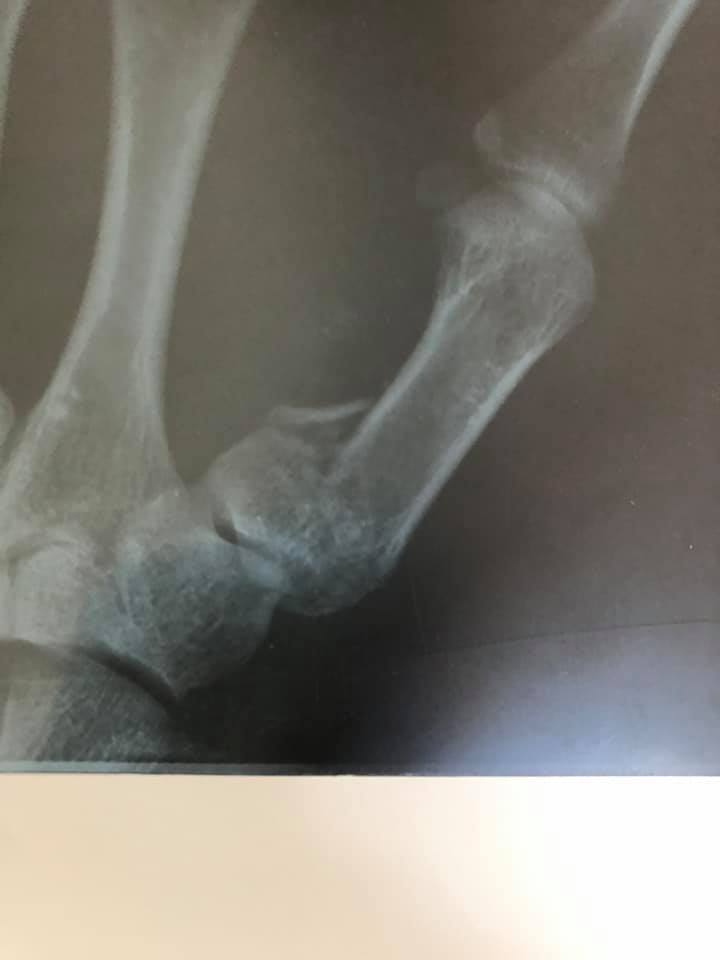

Пацієнт з висоти росту впав на землю. В ургентному порядку був оглянутий в КНП «НЦМЛ». Після огляду лікарем був встановлений діагноз: закритий перелом І п’ясної кістки правої кисті.

Волинянину провели оперативне лікування: остеосинтез п’ясної кістки та фіксація титановою міні-пластиною.